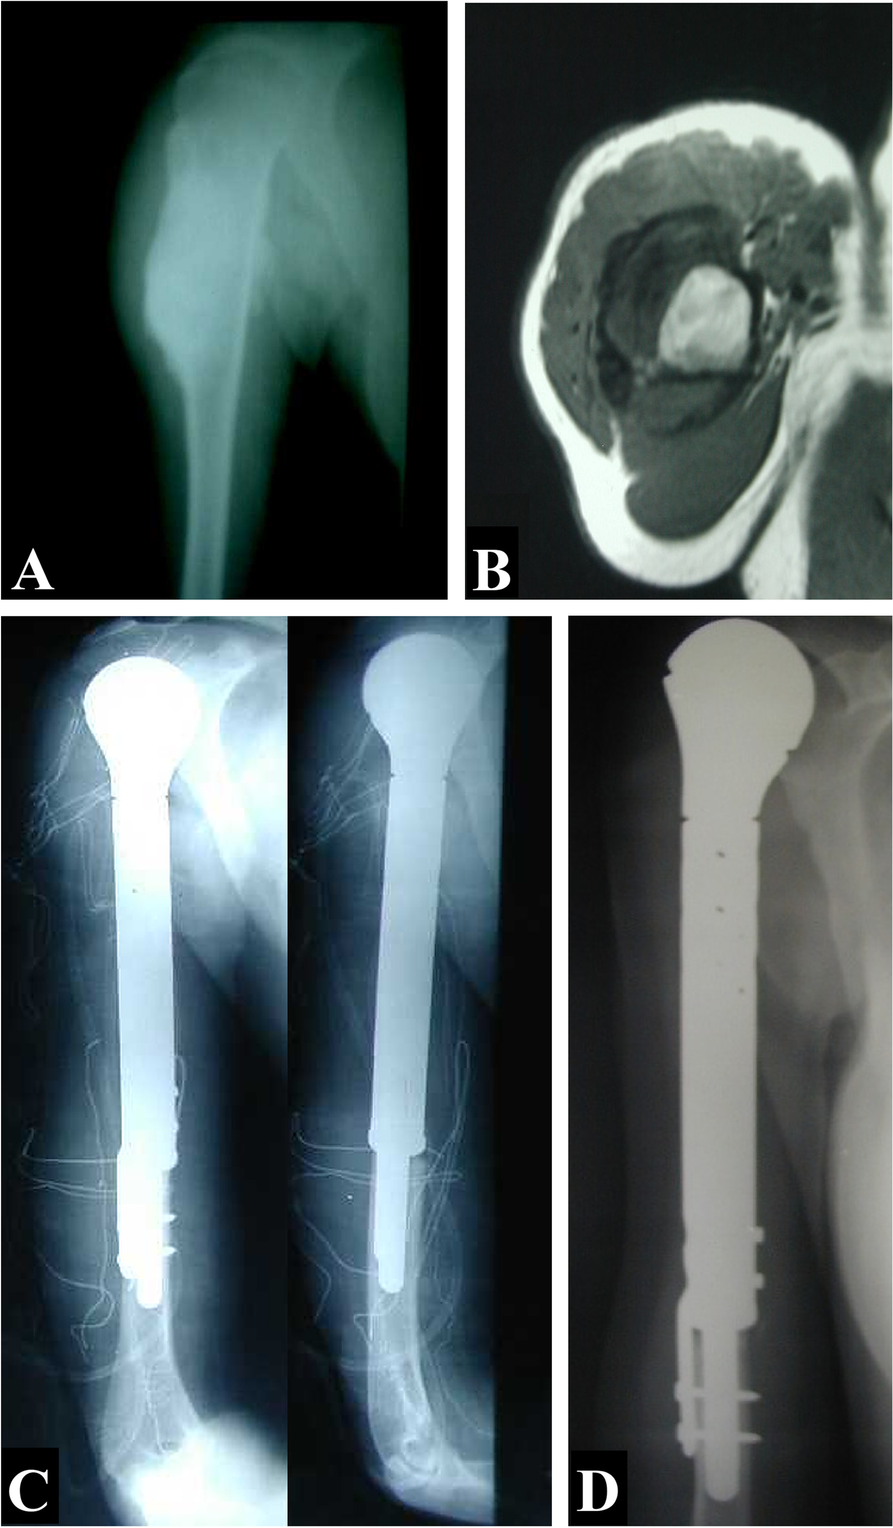

Background There is no agreement about the best reconstructive option following resection of proximal humerus tumors. The purpose of this study was to compare the functional outcomes of endoprosthesis reconstruction versus nail cement spacer reconstruction after wide resection of proximal humeral tumors. Methods This retrospective comparative study included 58 patients with proximal humerus tumors who had undergone tumor resection and reconstruction with modular endoprosthesis (humeral hemiarthroplasties) or cement spacer. Medical records were reviewed for the epidemiological, clinical, radiological, and operative data. Lung metastasis, local recurrence, and complication were also reviewed. The functional outcome was evaluated using the Musculoskeletal Tumor Society scoring (MSTS) system. Results Nineteen patients with a mean age of 33.4 ± 17.5 years underwent reconstruction by modular endoprosthesis, and 39 patients with a mean age of 24.6 ± 14.3 years underwent reconstruction by cement spacer. The mean MSTS score was 24.8 ± 1.1 in the endoprosthesis group and 23.9 ± 1.4 in the spacer group, P = 0.018. Complications were reported in 5 (26.3%) patients in the endoprosthesis group and 11 (28.2%) patients in the spacer group, P = 0.879. There were no statistically significant differences in the functional outcomes in both patient groups with or without axillary or deltoid resection. Conclusions Both endoprostheses and cement spacers are durable reconstructions with almost equal functional outcomes with no added advantage of the expensive endoprosthesis.

In our retrospective comparative study published in BMC Musculoskeletal Disorders, we evaluated outcomes in 58 patients who underwent limb-salvage surgery for proximal humerus tumors:

• 19 patients reconstructed with modular endoprosthesis (humeral hemiarthroplasty)

• 39 patients reconstructed with nail cement spacer

1.     Mean MSTS score:

– Endoprosthesis: 24.8 ± 1.1

– Cement spacer: 23.9 ± 1.4

→ Statistically significant difference (P = 0.018), but clinically modest

2.    Complication rates were comparable:

– Endoprosthesis: 26.3%

– Cement spacer: 28.2%

3.    No significant functional differences were observed in patients with or without axillary nerve or deltoid resection.

Both modular endoprostheses and cement spacers provided durable limb-salvage reconstruction with nearly equivalent functional outcomes.

Importantly, our findings suggest no substantial added functional advantage of the more expensive modular endoprosthesis, particularly in settings where cost considerations are relevant.